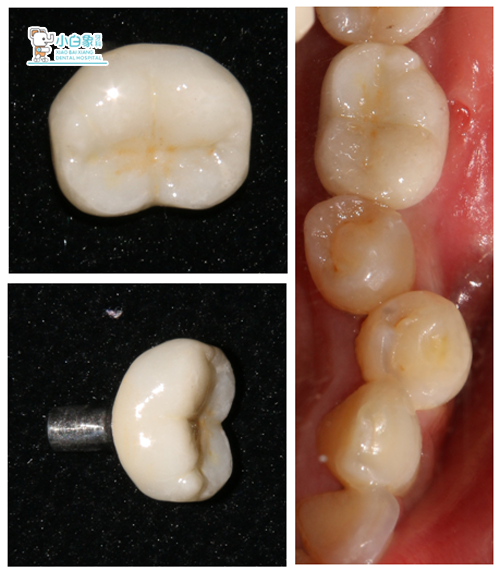

2017年12月25日 36取模

2018年2月1日 戴牙